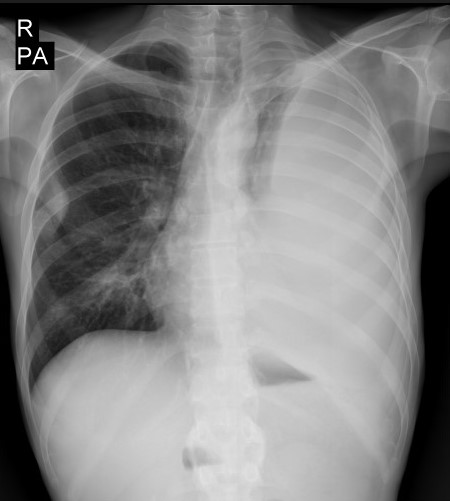

В клинику №1 ВиТерра Беляево обратился пациент, 42 года, с целью провести рентгенографию органов грудной клетки. На приёме у доктора пациент предъявлял жалобы на кашель с мокротой, затруднённое дыхание, повышение температуры тела, беспокоящие его на протяжении последнего месяца. Также отмечались слабость, повышенная утомляемость при физической нагрузке.Первое исследование

Врачом-рентгенологом Якушевой И.А. было выполнено исследование грудной клетки в 2-х проекциях.